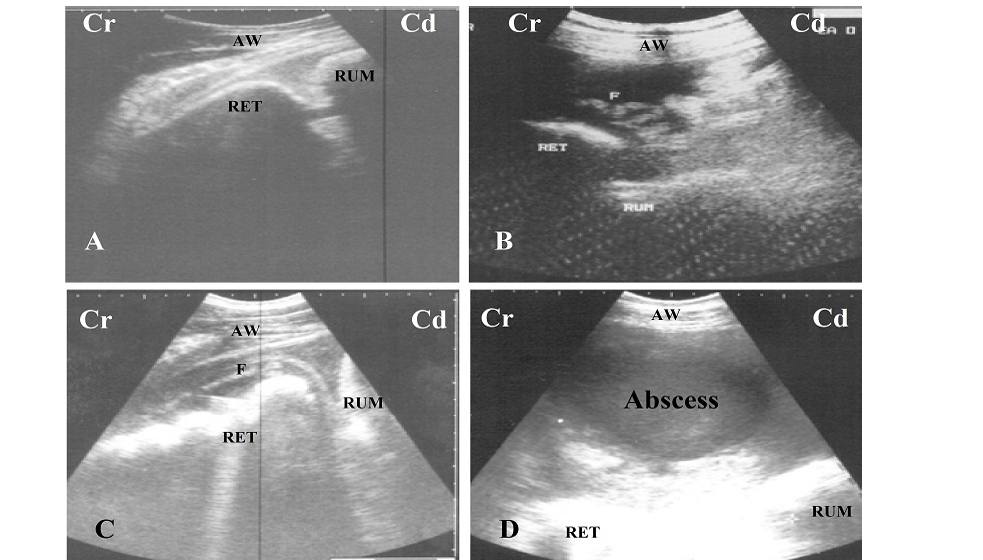

A. Ultrasonogram of normal reticulum during relaxation, it appears a half moon shaped;

B and C. Ultrasonogram of reticulum in case of foreign body syndrome, it appears corrugated and surrounded by inflammatory echogenic fibrin (F);

D. circumscribed abscess with echogenic capsule and hypoechoic pus content locates between reticulum (RET), rumen (RUM) and abdominal wall (AW); Cr: cranial; Cd: cauadal.